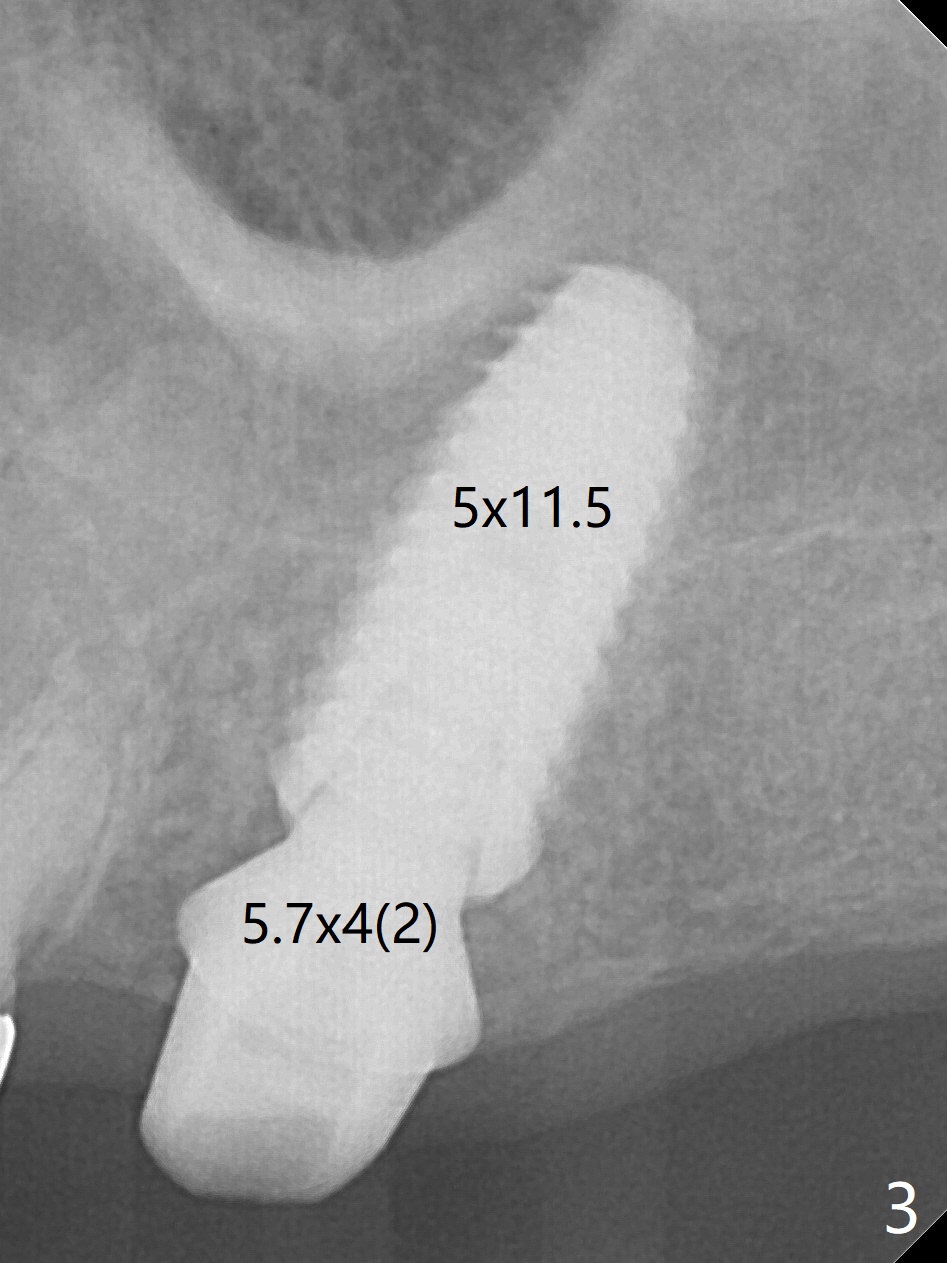

After extraction at #15 with 9 mm offset, a 12 mm bone trimmer is used to create a dimple in the septum. When a 4x7.3 mm drill is done according to drill sequence, initial osteotomy has no palatal wall. A 4.5x10 mm dummy implant cannot engage for sinus lift. DIO Sinus Approaching drill cannot enter IS green metal sleeve. When a 4x8.5 mm drill is finished, the sinus floor is intact. This is not the case when a 2.2x10 mm drill is used. Water membrane lifter does not seal the osteotomy (palatal defect). The 4.5x10 mm dummy implant is used for sinus lift, followed by 2-3 Amalgam carriers of allograft lifted with the same implant (Fig.1,2). After 4x10 mm drill and 2-3 carriers of Vanilla graft, a 5x11.5 mm implant is placed >55 Ncm with immediate placement of a 5.7x4(2) mm abutment (Fig.3). With sticky bone and 2 pieces of PRF in the remaining socket, an immediate provisional is fabricated and seated. When the patient returns for impression nearly 6 months postop, she feels mild pain. In fact the temporary crown/abutment is loose and traps food underneath with the erythematous gingival cuff. A 5.7x4(3) mm abutment is placed and torqued without gap for impression (no temp); the implant threads are exposed distal (Fig.4 <). Retrospectively, the incompletely seated cemented abutment should be tightened ~ 1 month postop when the socket heals.